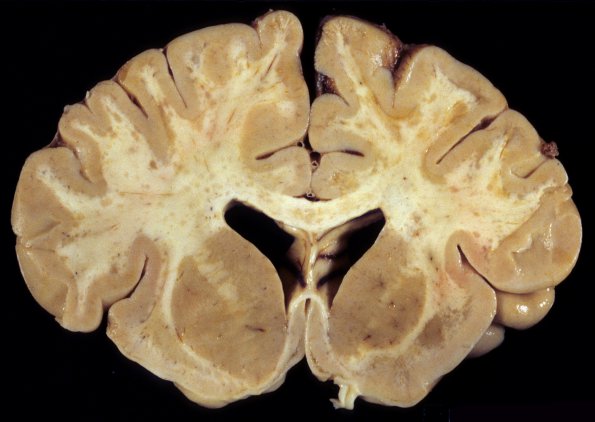

1A1,2 In this case there is extensive fluffy lesions in the white matter of the centrum semiovale which extend into the deep cortex. Notice the absence of U fiber sparing (arrow, 1A2)